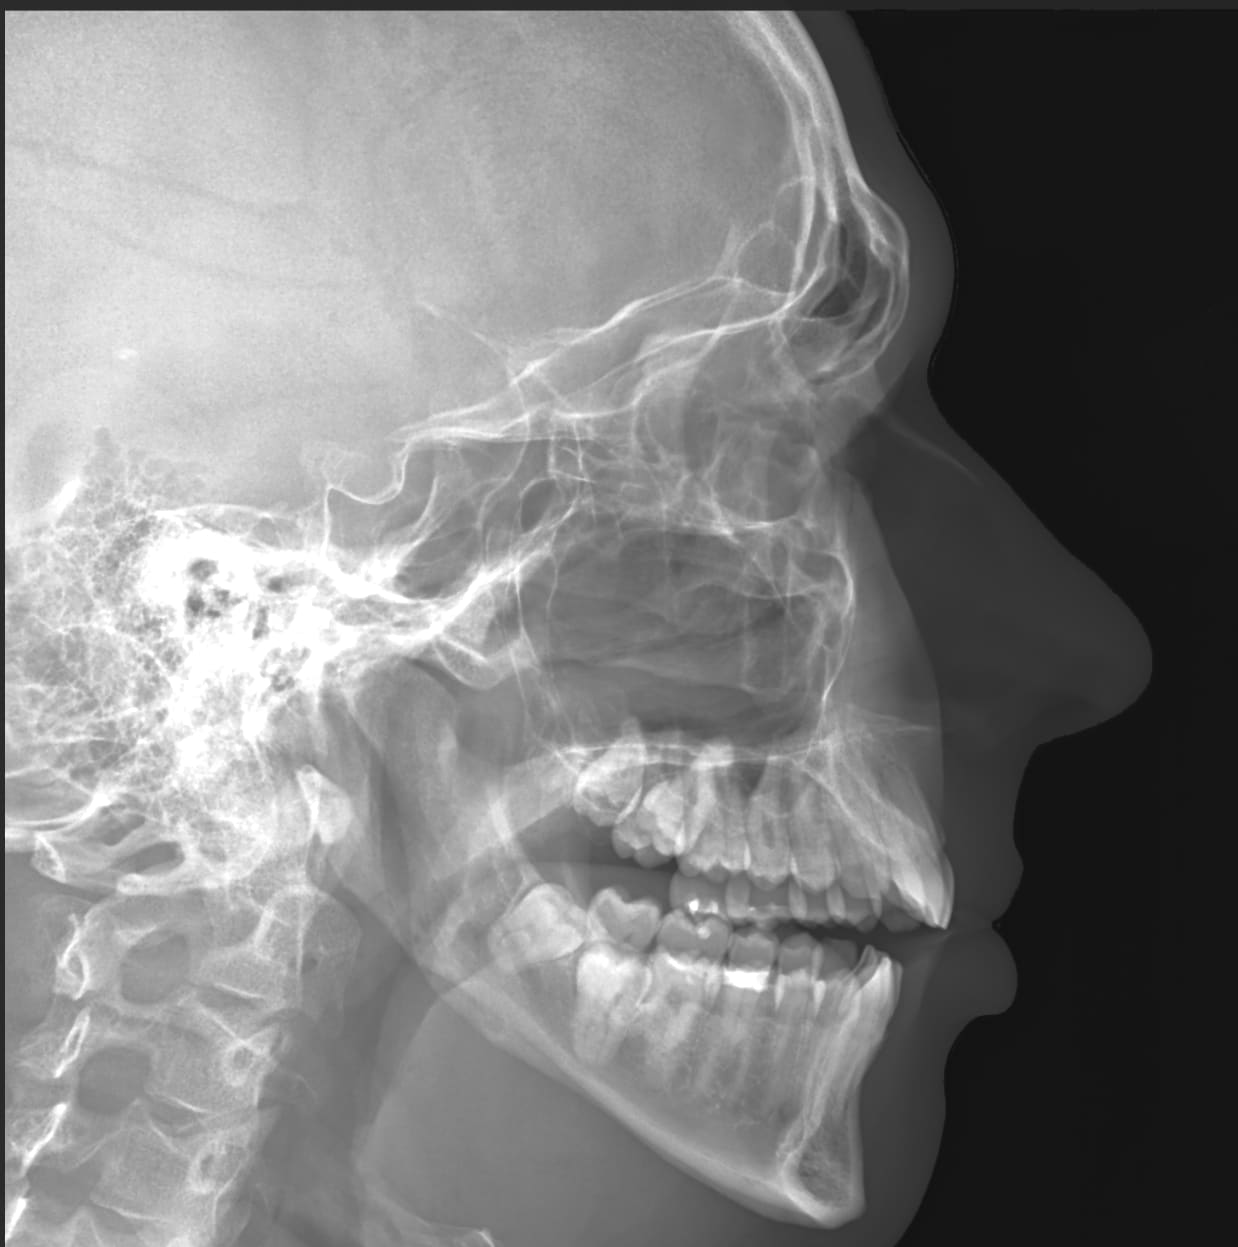

Just got my head xrayed for unrelated reasons. Check out my enlightened wisdom pointing in all which-ways

@Moose it’s weird to see your skull. Is it weird for you?

@katylava @Moose nnoooo it is totally cool to see ones skull and how it lines up with the outline of their face.

@Moose

@medz @Moose

@medz stop messing with my head!